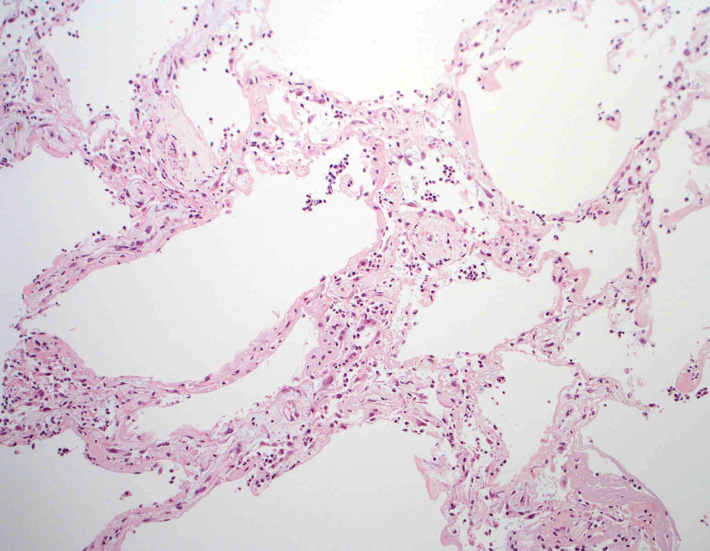

肺の病理所見

lung01.jpg

lung02.jpg

lung03.jpg

lung04.jpg

Fig.01Fig.02Fig.03Fig.04